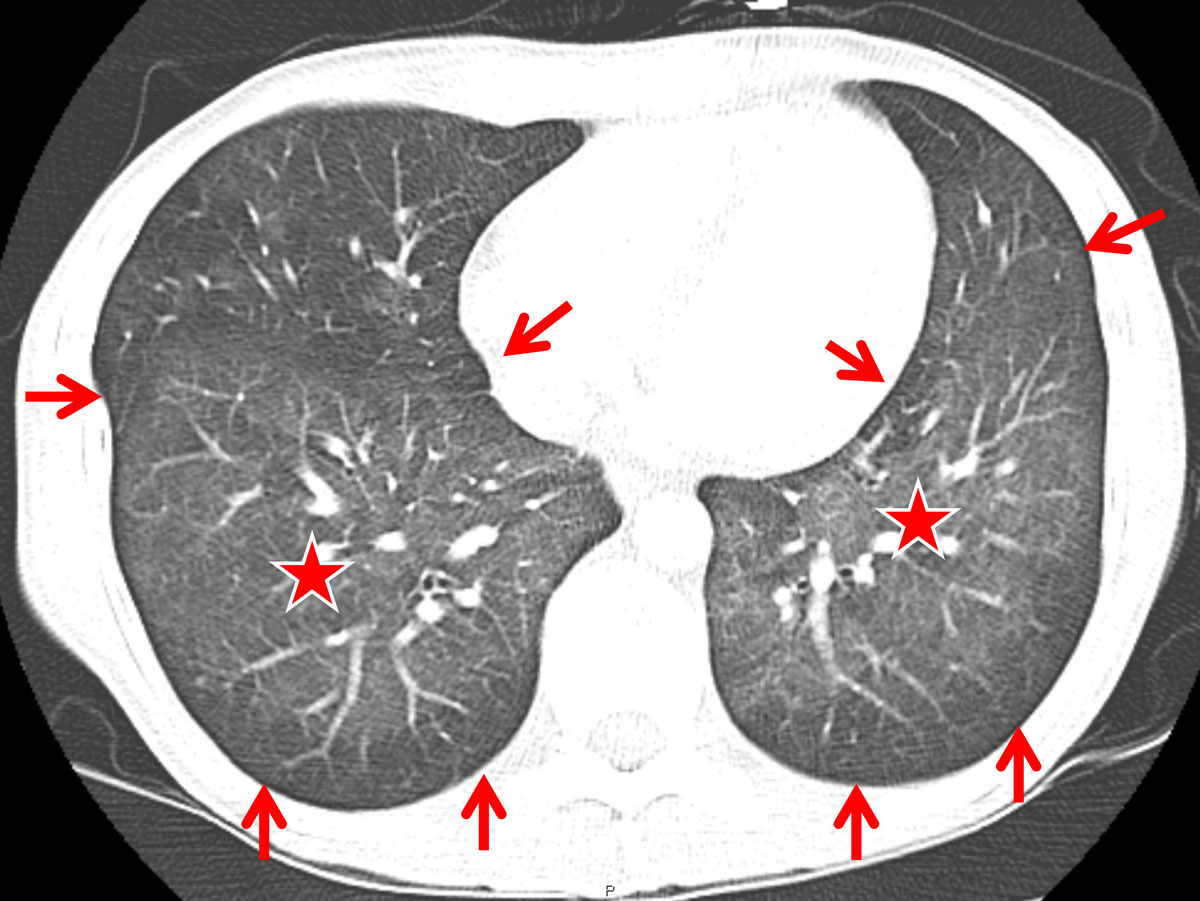

In comparison, the HIV-positive patients with PJP showed significantly more areas of atelectasis (41.7 ± 6.4%, vs 4.2 ± 4.1% in RTRs, p = 0.017; table 2). Furthermore, HIV patients tended to present with a more “classic” pattern of PJP, exhibiting subpleural sparing (fig. 2) and additional hilar lymph node enlargement (23.3 ± 5.5%; fig. 3). Pneumothorax formation was restricted to 3.3% of the HIV-positive patients. When the results from the conservative Bonferroni method were compared with the results from a multi-variable analysis, significantly more cysts could be found in HIV than in RTR cases (15.0 ± 4.6% vs 4.2 ± 4.1%, p = 0.038; table 2). An analysis of the disease distribution within each lung segment between the two cohorts did not yield any statistically significant results (table 2).

Figure 2 Computed tomography (CT) findings in a human immunodeficiency virus-positive patient suffering from Pneumocystis jirovecii pneumonia (PJP) (axial CT section at the level of the lung bases): diffuse ground glass opacity (asterisk) and subpleural sparing (arrows) was found to represent a more or less classic CT-pattern for PJP.